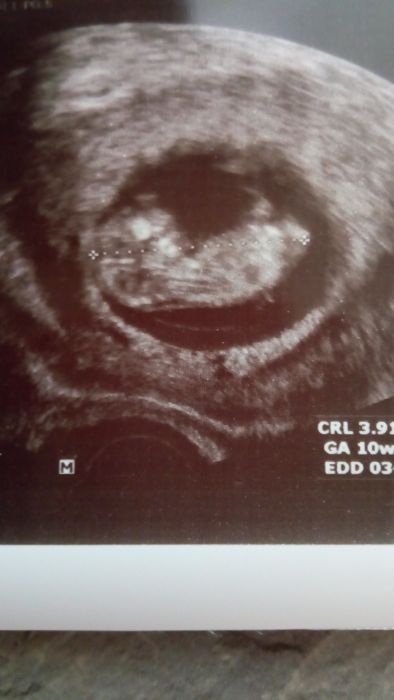

Tak dnešní kontrola dopadla dobře, jsem 10+6tt, viděla jsem prcka jak sebou krásně mrskal a je tam teda nakonec jen jeden, tak přítel si oddychl

Domluvili jsme se na neschopenku k 1.10., tak se i docela těším, protože ta únava je opravdu hrozná. Přidávám fotečku